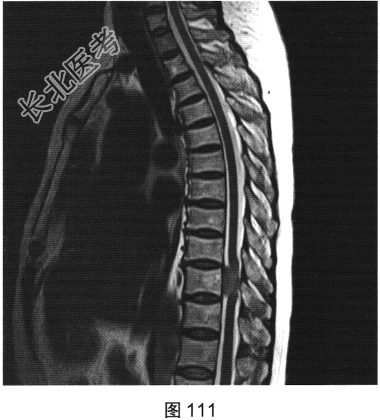

- [材料题] 患者女性,59岁,无明显诱因出现腰背部疼痛伴双下肢麻木1年,久行、久坐、久站或咳嗽、排便时疼痛加重,休息后症状缓解,1个月前腰背部麻木疼痛突发加重,行走100米既感疼痛难忍,伴双下肢无力疼痛。查体:脊柱无明显侧弯,相当于T₁₀平面以下感觉减退,腰椎活动度受限,无紧张,棘突旁压痛、叩痛,向双下肢放射。挺腹试验阳性,跟臀试验(+),双侧直腿抬高试验(一),双下肢小腿外侧、足背感觉稍差,双侧

背伸肌肌力4级;肌张力正常,双侧巴宾斯基征可疑阳性。实验室检查:人类白细胞抗原B27阴性(一),RF<10U/ml(正常值0~15U/ml)。

- 简答题2、患者行MRI检查,如图111~图114所示。根据患者病史及影像学检查,请问其最可能的诊断是什么?

- 简答题3、请对脊膜瘤进行描述。